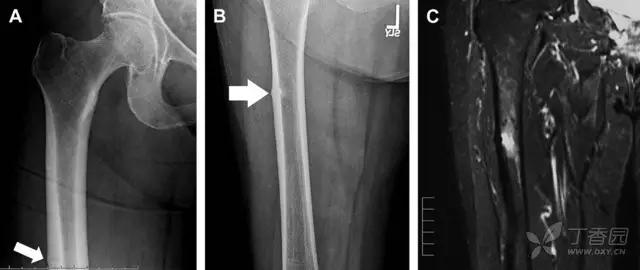

股骨颈应力性骨折

股骨颈应力性骨折在参加耐力运动的运动员中常见,且常发生在股骨颈压力侧。股骨颈基底部发现一垂直于骨皮质的线性硬化带可诊断这种类型的疲劳性骨折(图 8)。

图 8 长跑运动员股骨颈应力性骨折。X 片(A)和冠状位 CT 多维重建(B)图像示穿过股骨颈内侧皮质中的透亮区(箭头),周围硬化。骨折垂直于皮质

股骨颈张力侧的应力性骨折有可能发展为完全骨折(图 9)。

图 9 进食障碍患者股骨颈应力性骨折的张力侧。A 正位片示股骨颈完全骨折。B 2 周前的 X 片示局部骨量减少,正是后来发生骨折的位置(箭头)

非典型股骨骨折

另一种易漏诊的骨折是非典型股骨骨折,这种骨折与长期服用双膦酸盐相关,常发生在使用双膦酸盐 3 年以上的患者。前驱症状表现为腹股沟痛或大腿痛的患者中,60%~70% 被错误地认为由腰背痛或髋关节炎引起。

这种骨折的一个典型表现为火山口状骨膜隆起及一横行透亮带。值得注意的是,超过 50% 的患者表现为股骨干完全骨折。由于 50%~60% 的患者会累及双侧,所以一旦一侧下肢确诊,需行对侧下肢检查。

图 10 老年患者长期服用双磷酸盐引起的骨折。A 髋部正位片,箭头所示,股骨外侧皮质存在横行透亮带。B 后续的股骨 X 线片示局灶性骨膜反应,以及此类骨折的特征性表现-火山口状骨膜隆起(箭头)。C MRI 冠状位 STIR 序列扫描示相应骨折平面的骨髓水肿表现